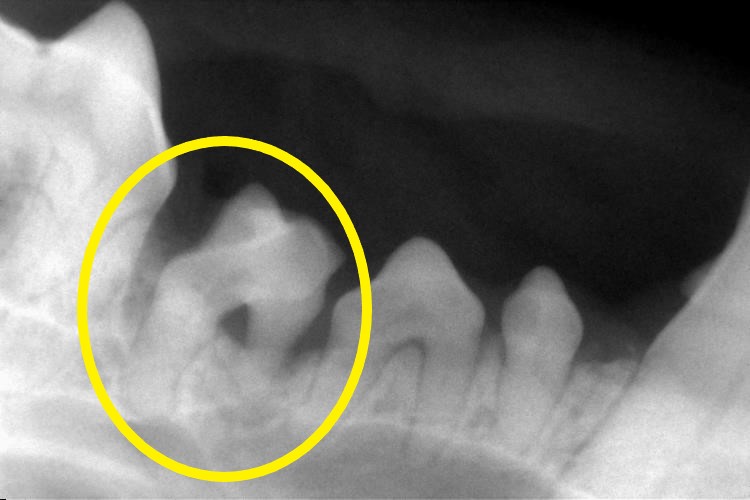

下の写真は下顎臼歯のレントゲンです。

〇印の歯は歯槽骨が溶け、ぐらついていました。

歯のぐらつきは痛みの原因となります。

痛みを取り除くため、抜歯処置を行いました。